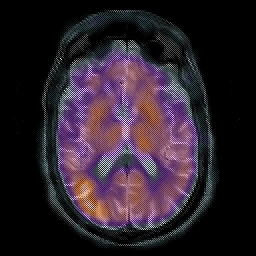

Subacute Stroke overlay -- Slice #12

[Home][Help][Clinical] Slice 12